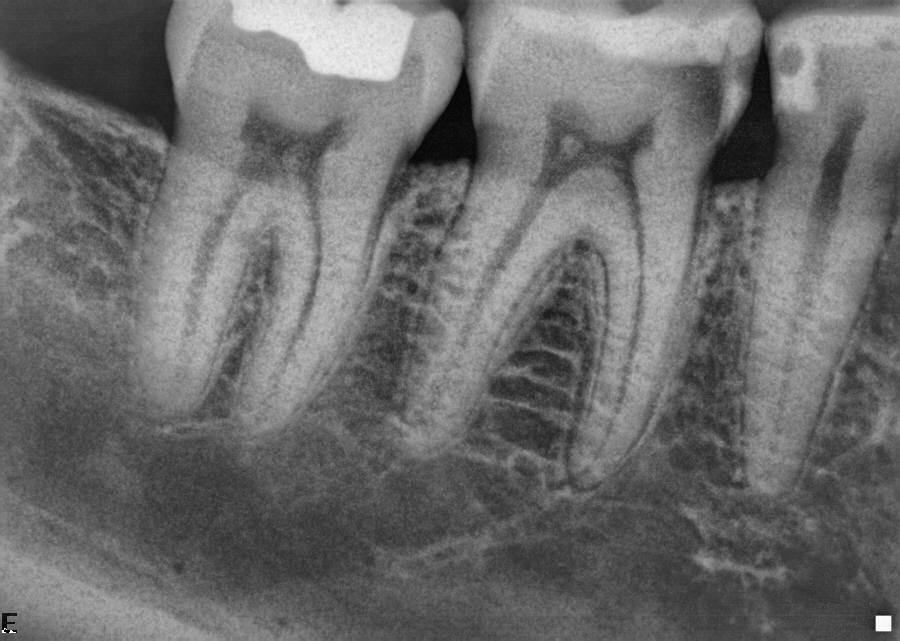

Interne resorptie

Apicale wortelresorptie

Externe resorptie

Pulpasclerose

Pulpolieten

Hypercementose